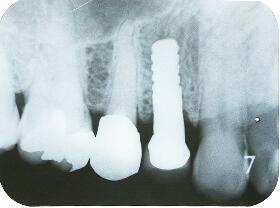

インプラント埋入手術直後のエックス線写真

・20分ほどで埋入終了

インプラント埋入後1ヵ月のエックス線写真

埋入直後と比べインプラント体頸部の骨の状態が安定してきた